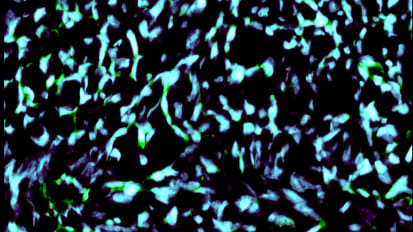

Tumor-infiltrating lymphocyte, or TIL, therapy uses a patient’s own immune system T cells to fight cancer.Modified Personalized Cancer Vaccine Generates Powerful Immune Response